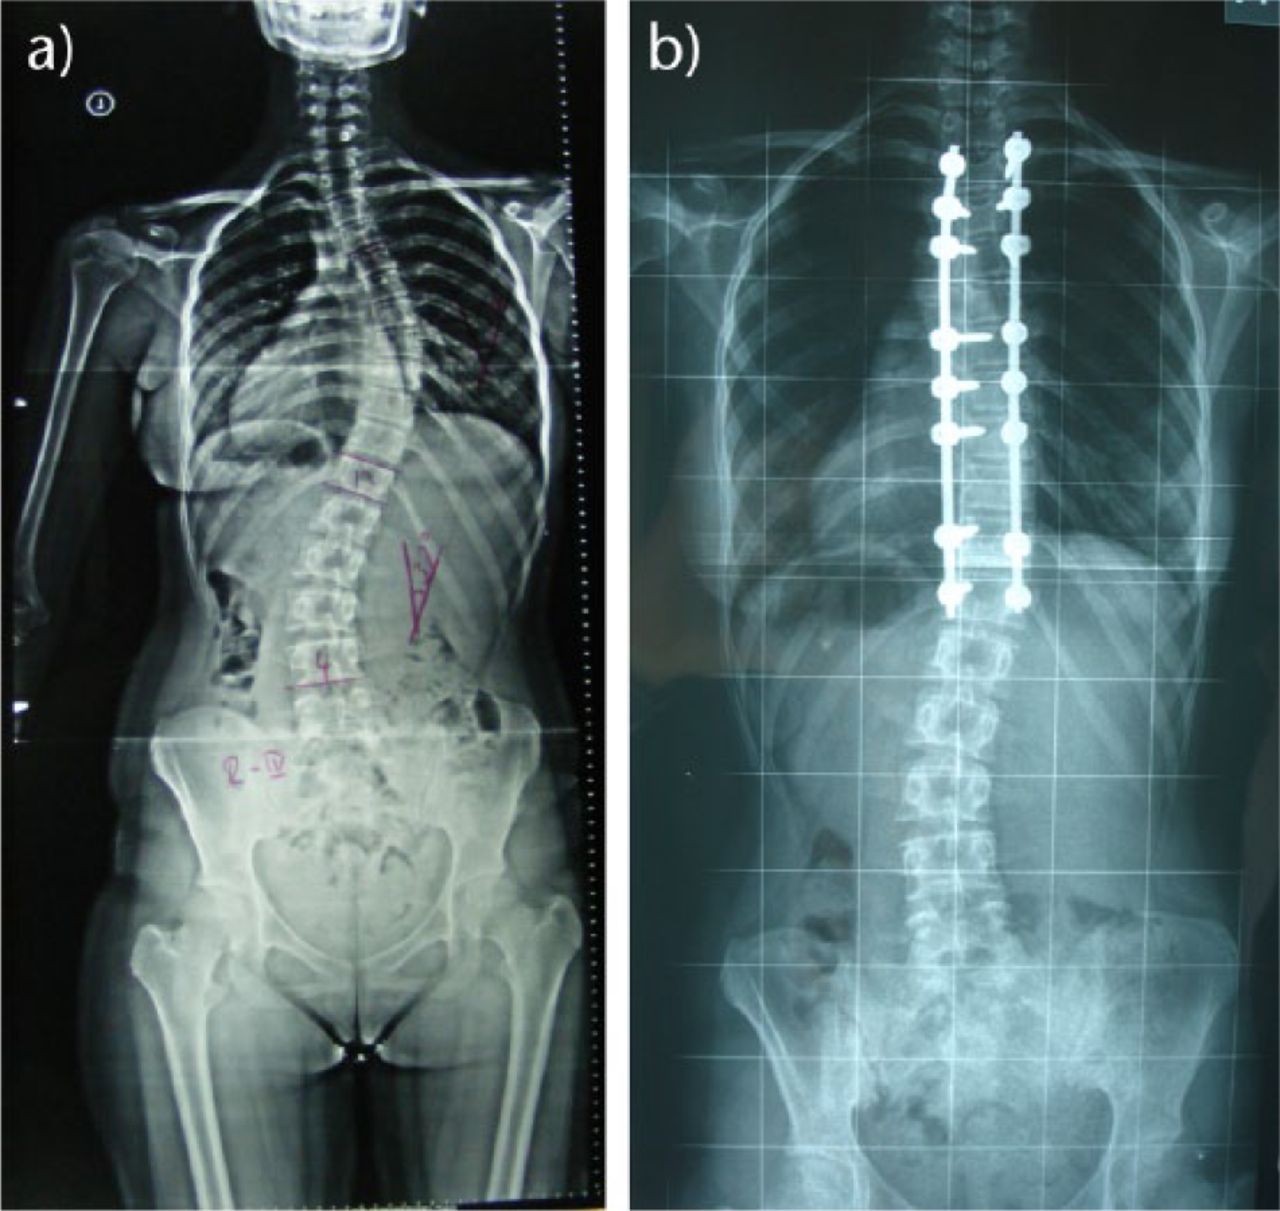

Spine deformity correction refers to surgery to correct deformed spine structures due to a number of different conditions. These can include both scoliosis and kyphosis, though the underlying cause of these conditions can range from defects not corrected at birth to injury, trauma and accidents. Deformity correct straightens curved sections of the spine and fuses the vertebrae to ensure further movement does not occur.